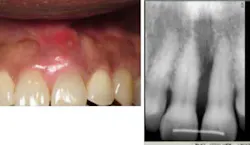

A 67-year-old African American female presented in 2001. Her diagnosis was chronic periodontitis and diabetes. Fear and anxiety resulted in refusal of osseous surgical care for bone regeneration and pocket reduction. Scaling was performed and the patient did not return for five years. She then presented with an abscess on No. 9 with significant bone loss that was not evident five years ago. Tooth No. 9 tested vital. The patient accepted the LANAP protocol. Treatment was done in January 2012.

Mrs. High Anxiety before the LANAP protocol.

Mrs. High Anxiety has returned for all postop appointments this time around. Her abscess has resolved and a small amount of bone regeneration is noted on the eight-month postop radiograph. If the bone fill is not better at one year, a retreatment of the site will be suggested. Tissue height, which was a major esthetic concern, has remained at an acceptable level for the patient.

Mrs. High Anxiety after treatment.